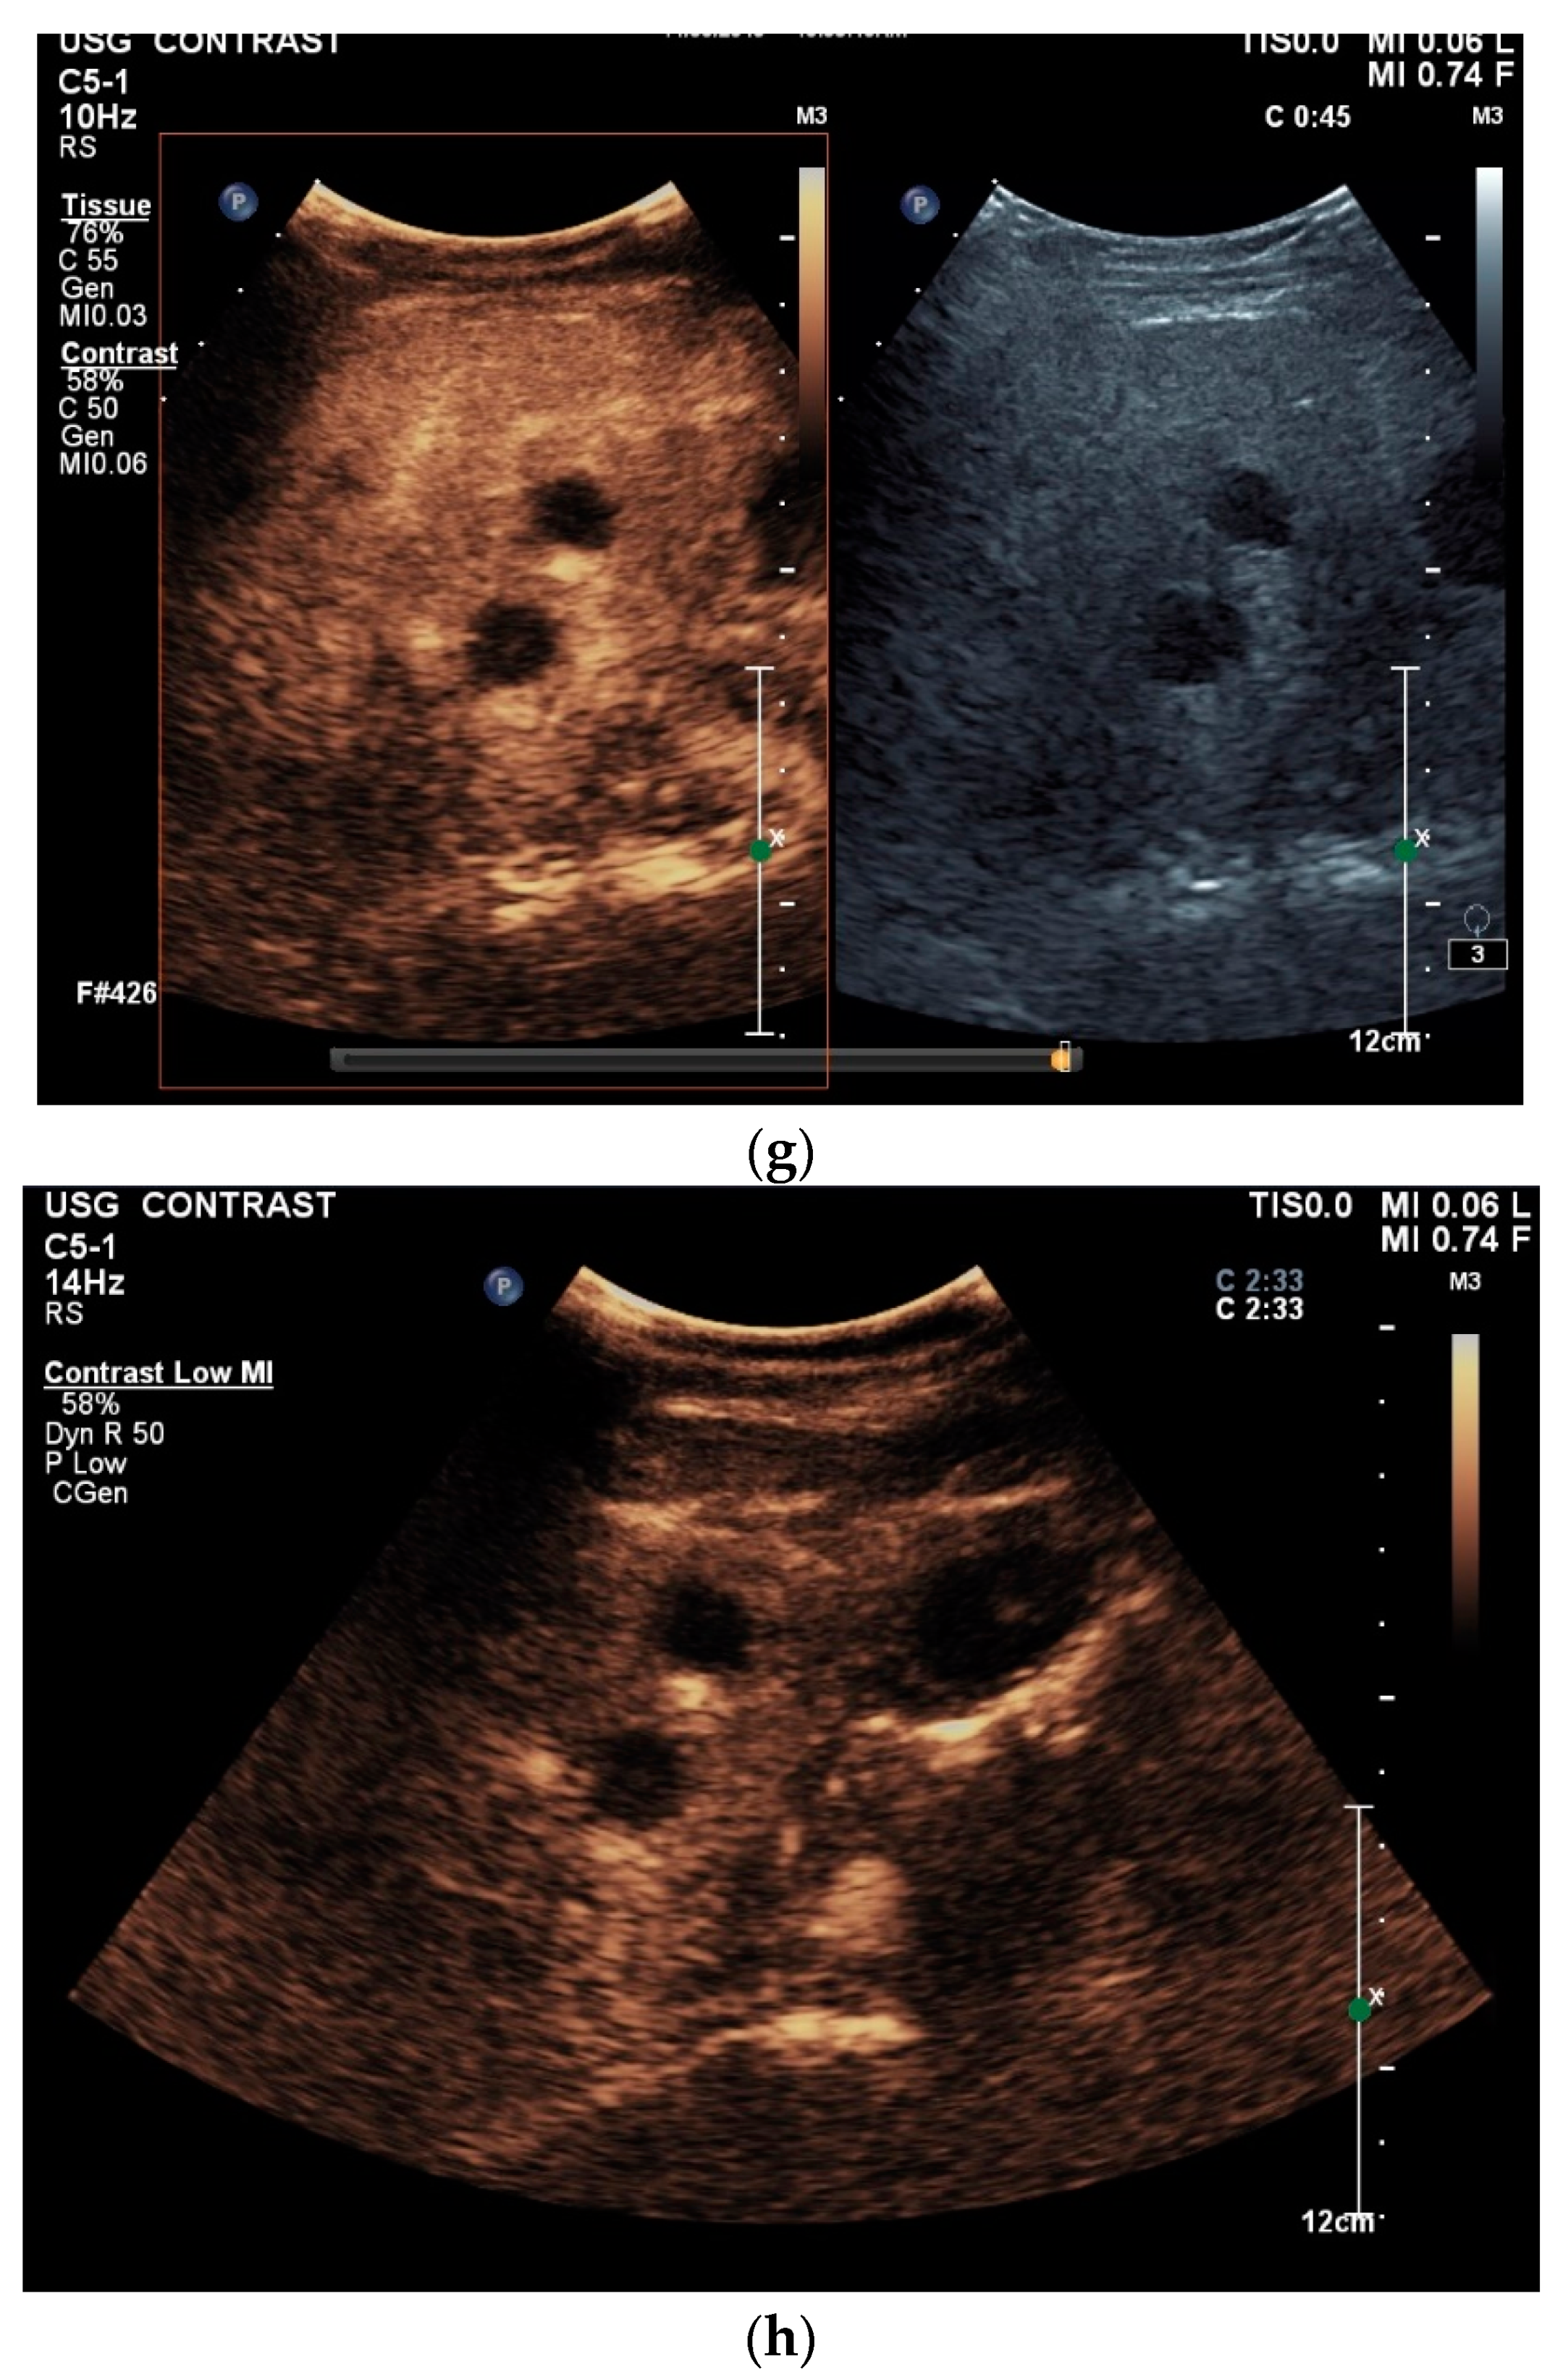

Spleen involvement usually only occurs in disseminated disease. The manifestations are splenomegaly, hypoechoic micronodular (miliary), or macronodular lesions [8,74], as well as splenic abscesses [75] [Figure 4a–d]. In a group of patients with tuberculosis and mostly advanced HIV infection, 37% had splenic lesions [5]. In 33%, splenic lesions were associated with lymphadenopathy, and 16% each had splenic lesions and ascites or splenic lesions, ascites, and lymphadenopathy. Micronodular lesions may be indistinguishable. If this is suspected, examination with a high-resolution linear transducer is recommended. Using CEUS, splenic lesions in the arterial phase showed a hyperenhancement, followed by either a slow washout or a persistent enhancement in the middle and late parenchymal phase [76]. A fast washout was the exception, but nevertheless was also possible. These exceptional cases would therefore be difficult to differentiate from malignancies. There was also rim-like enhancement with central nonenhancement, like abscesses and septation-like enhancement [76]. Another study using CEUS in splenic manifestations of tuberculosis presented homogeneous enhancement (6.7%), heterogeneous enhancement (63.3%), and nonenhancement (30.0%). Most of the cases showed low enhancement. Among these cases, heterogeneous enhancement was divided into septal enhancement type (21.1%) and marginal enhancement type (78.9%) [77] [Figure 4c–g]. The most important differential diagnoses are non-Hodgkin’s lymphoma and other granulomatous inflammations, such as sarcoidosis, especially in the presence of lymphadenopathy. The splenic lesions must be differentiated from mycotic abscesses, leukemic infiltrates, and metastases. In the meta-analysis conducted by van Hoving et al. [78], splenic lesions as manifestations of abdominal tuberculosis had a broad sensitivity of 13–62% in five studies using B-mode ultrasonography. The specificity was higher, at 86–100%.

Figure 4.

Sonographic and CEUS features of splenic tuberculosis. Sonographic and CEUS features of splenic tuberculosis. Subcapsular splenic lesion (arrow) (a), subcapsular splenic lesion using a linear transducer of 12 MHz (arrows) (b). Histologically confirmed tuberculosis from mediastinal lymph nodes. Multiple small splenic lesions (c). Using CEUS with a linear transducer (9 MHz), these are slightly hypoenhanced in the arterial phase (d), and show a progressive washout in the course of the venous phase (arrows) (e). Subcapsular splenic lesion (arrow) with nonenhanced and hypoenhanced parts and hyperenhanced rims indicate a caseous necrosis (f). In another section, an interrupted spleen capsule (arrow) due to a rupture of the caseous necrosis can be assumed (g).